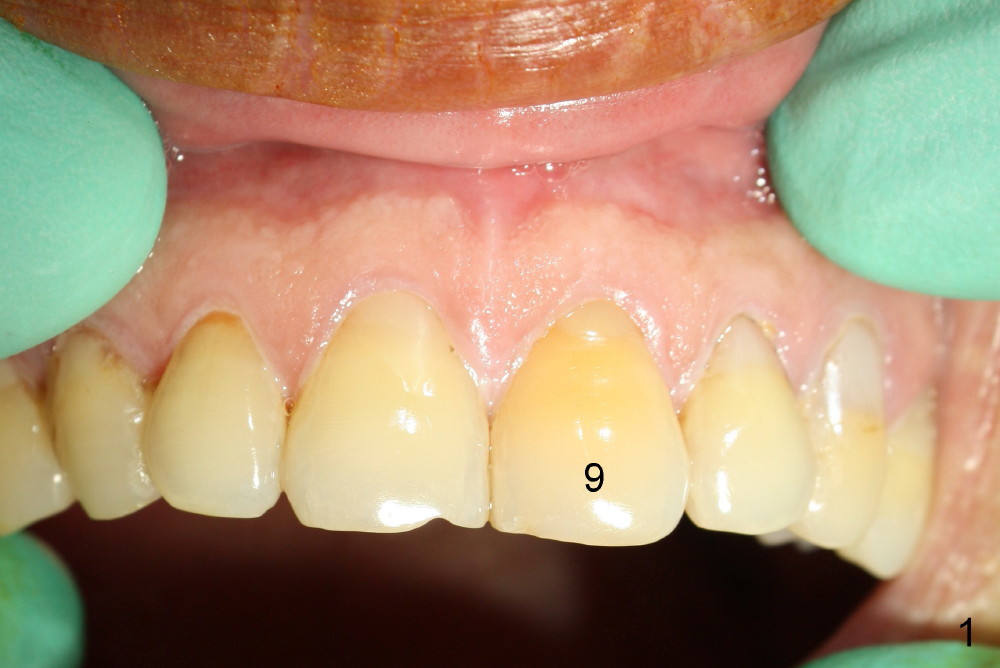

A 65-year-old man had injury to the tooth #9 20 years ago. The tooth has been discolored since (Fig.1). The tooth remained asymptomatic until last year. It has been loose since then. X-ray shows short root (Fig.2 S), sclerosed canal and bone loss mesially. There is a lingual abscess (Fig.8 A) with deep pockets.

Postop tenderness lasts for two days. The palatal swelling is unnoticeable 7 days postop (Fig.9 *, as compared to A in Fig.8). The bone remains stable around the implant (Fig.10), while the gingiva healthy around the immediate provisional (Fig.11) 5 months postop. Due to insurance limit, the permanent restoration is delayed (16 months postop, Fig.12). The patient is satisfied with the function and appearance 3 years 8 months postop (21 months post cementation, Fig.13,14). PA is taken 4 years 1 month postop (2.5 years post cementation, Fig.15). The lamina dura forms from the most coronal threads (Fig.16). Although there is no bone loss around the implant (Fig.17), metal starts to show 5 years 2 months postop (Fig.18 ^), probably related to the buccal placement, too large the implant for the site or buccal plate atrophy (Fig.19).